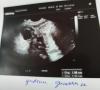

Сходила на узи, нашли кисту, нашли доминантный фолликул, больше ничего не нашли😁 Сижу на низком старте

@olyavpole можно фото самого УЗИ?

стикер